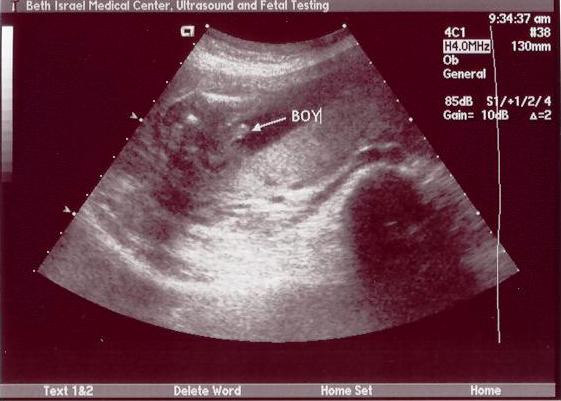

Re: sono pics of boys

Here's our son. It was taken at 18 weeks 5 days.

ETA: The arrow is pointing to the family jewels

Message edited 7/28/2005 6:51:33 PM.